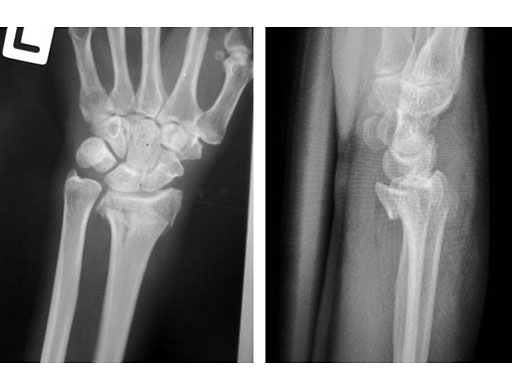

Fig 1a-b Preoperative x-rays